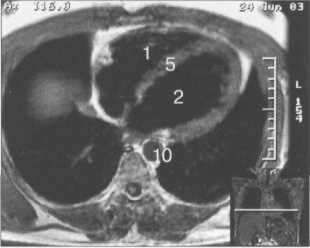

Рис. 9.48. MPT сердца. Сагиттальная плоскость.

Рис. 9.49. МРТ сердца. Двухкамерные сечения.

Рис. 9.50. МРТ сердца. Фронтальные сечения.

Рис. 9.51. МРТ сердца. Сечения по короткой оси левого желудочка.

Рис. 9.52. МРТ сердца. Четырехкамерные сечения.

На рис. 9.47—9.52 представлены Т1-ВИ наиболее часто используемых МР-сечений сердца.

Здесь и на рис. 9.48—9.52:

I — правый желудочек, 2 — левый желудочек, 3 — правое предсердие, 4 — левое предсердие, 5 — межжелудочковая перегородка, 6 — межпредсердная перегородка, 7 — задняя стенка левого желудочка, 8 — восходящая часть аорты, 9 — дуга аорты, 10 — нисходящая часть аорты, 11 — легочный ствол, 12 — правая легочная артерия. 13 — левая легочная артерия, 14 — верхняя полая вена, 15 — нижняя полая вена, 16 — трахея.